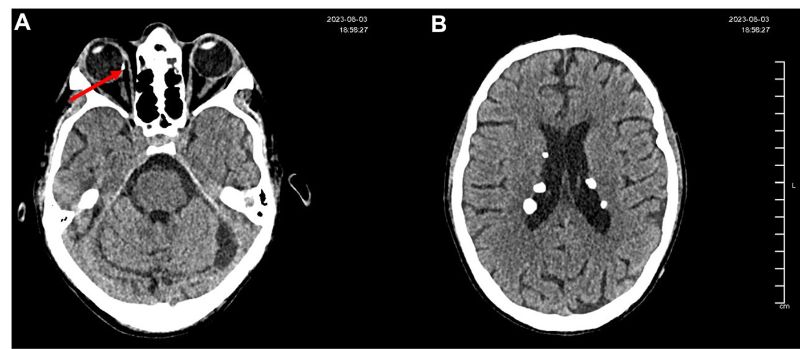

Figure 2A: Non-contrast axial cranial CT scan showing a hyperdense image compatible with retinal calcification in the nasal retina of the right eye, suggestive of a probable hamartoma.

Figure 2B: Non-contrast cranial CT scan showing multiple subependymal and parenchymal calcifications located in the lateral ventricles, left cerebellar hemisphere, and left temporal lobe. Lesions display features consistent with calcified hamartomas secondary to tuberous sclerosis, with no perilesional edema or associated mass effect.